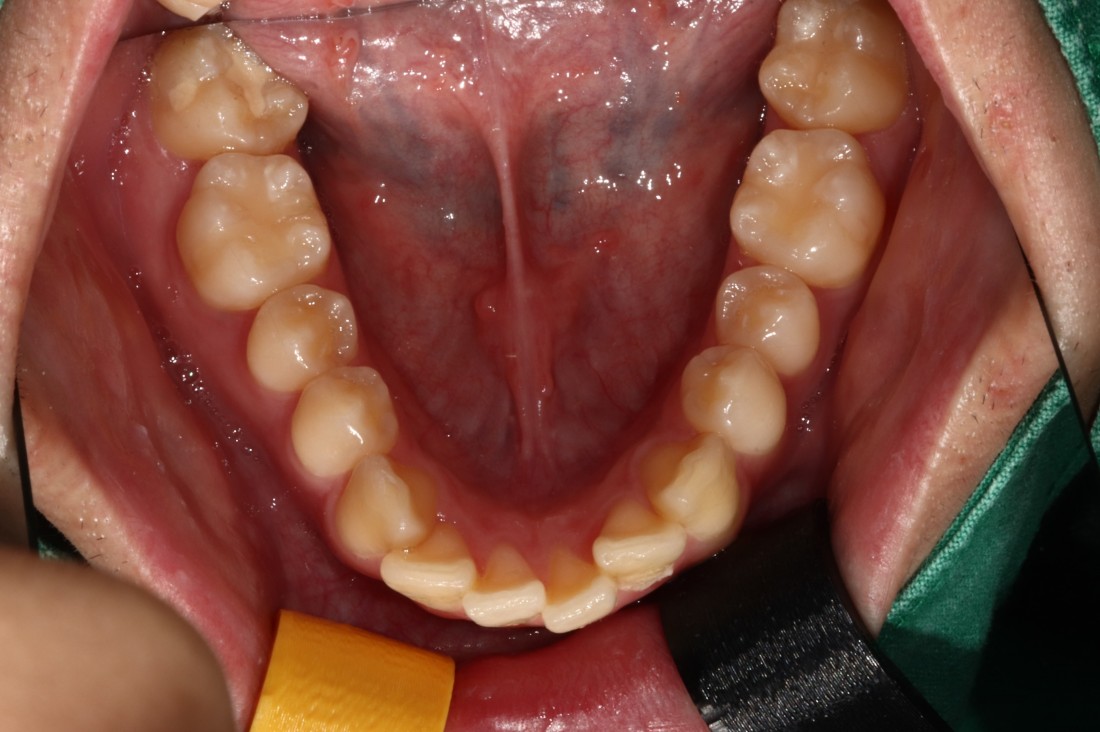

광주 개방교합 교정을 위해

방문해주신 30대 남성 환자분의

교정 전 사진입니다.

어금니를 맞닿게 하여서 입을 다물어도

윗니와 아랫니가 만나지 않는데요.